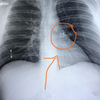

image Homem encontra piercing perdido há cinco anos ao fazer um raio-x; entenda

O homem pensava ser pneumonia, devido à falta de ar, mas tomou um susto ao descobrir que era o seu piercing que tinha ido parar no pulmão